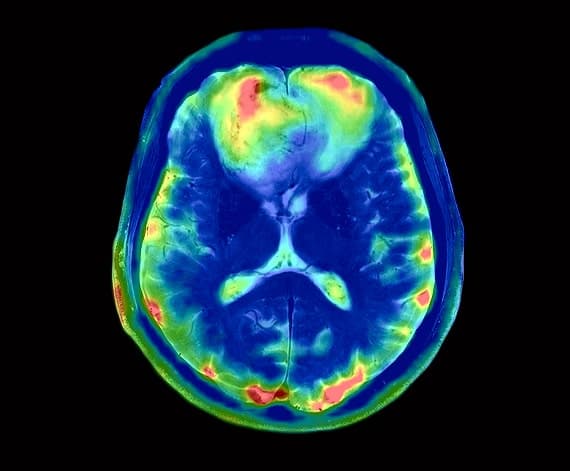

NeuroQuant®

Automated Brain Volume Analysis. NeuroQuant® provides FDA-cleared, objective measurements of brain structures. By quantifying volume changes, we help clinicians detect and track early-stage atrophy associated with Alzheimer’s, dementia, and epilepsy.

DTI (Diffusion Tensor Imaging)

Visualizing White Matter Integrity. Our DTI technology maps microscopic water movement in the brain to identify axonal shearing and subtle Traumatic Brain Injuries (TBI) that standard MRIs often miss.